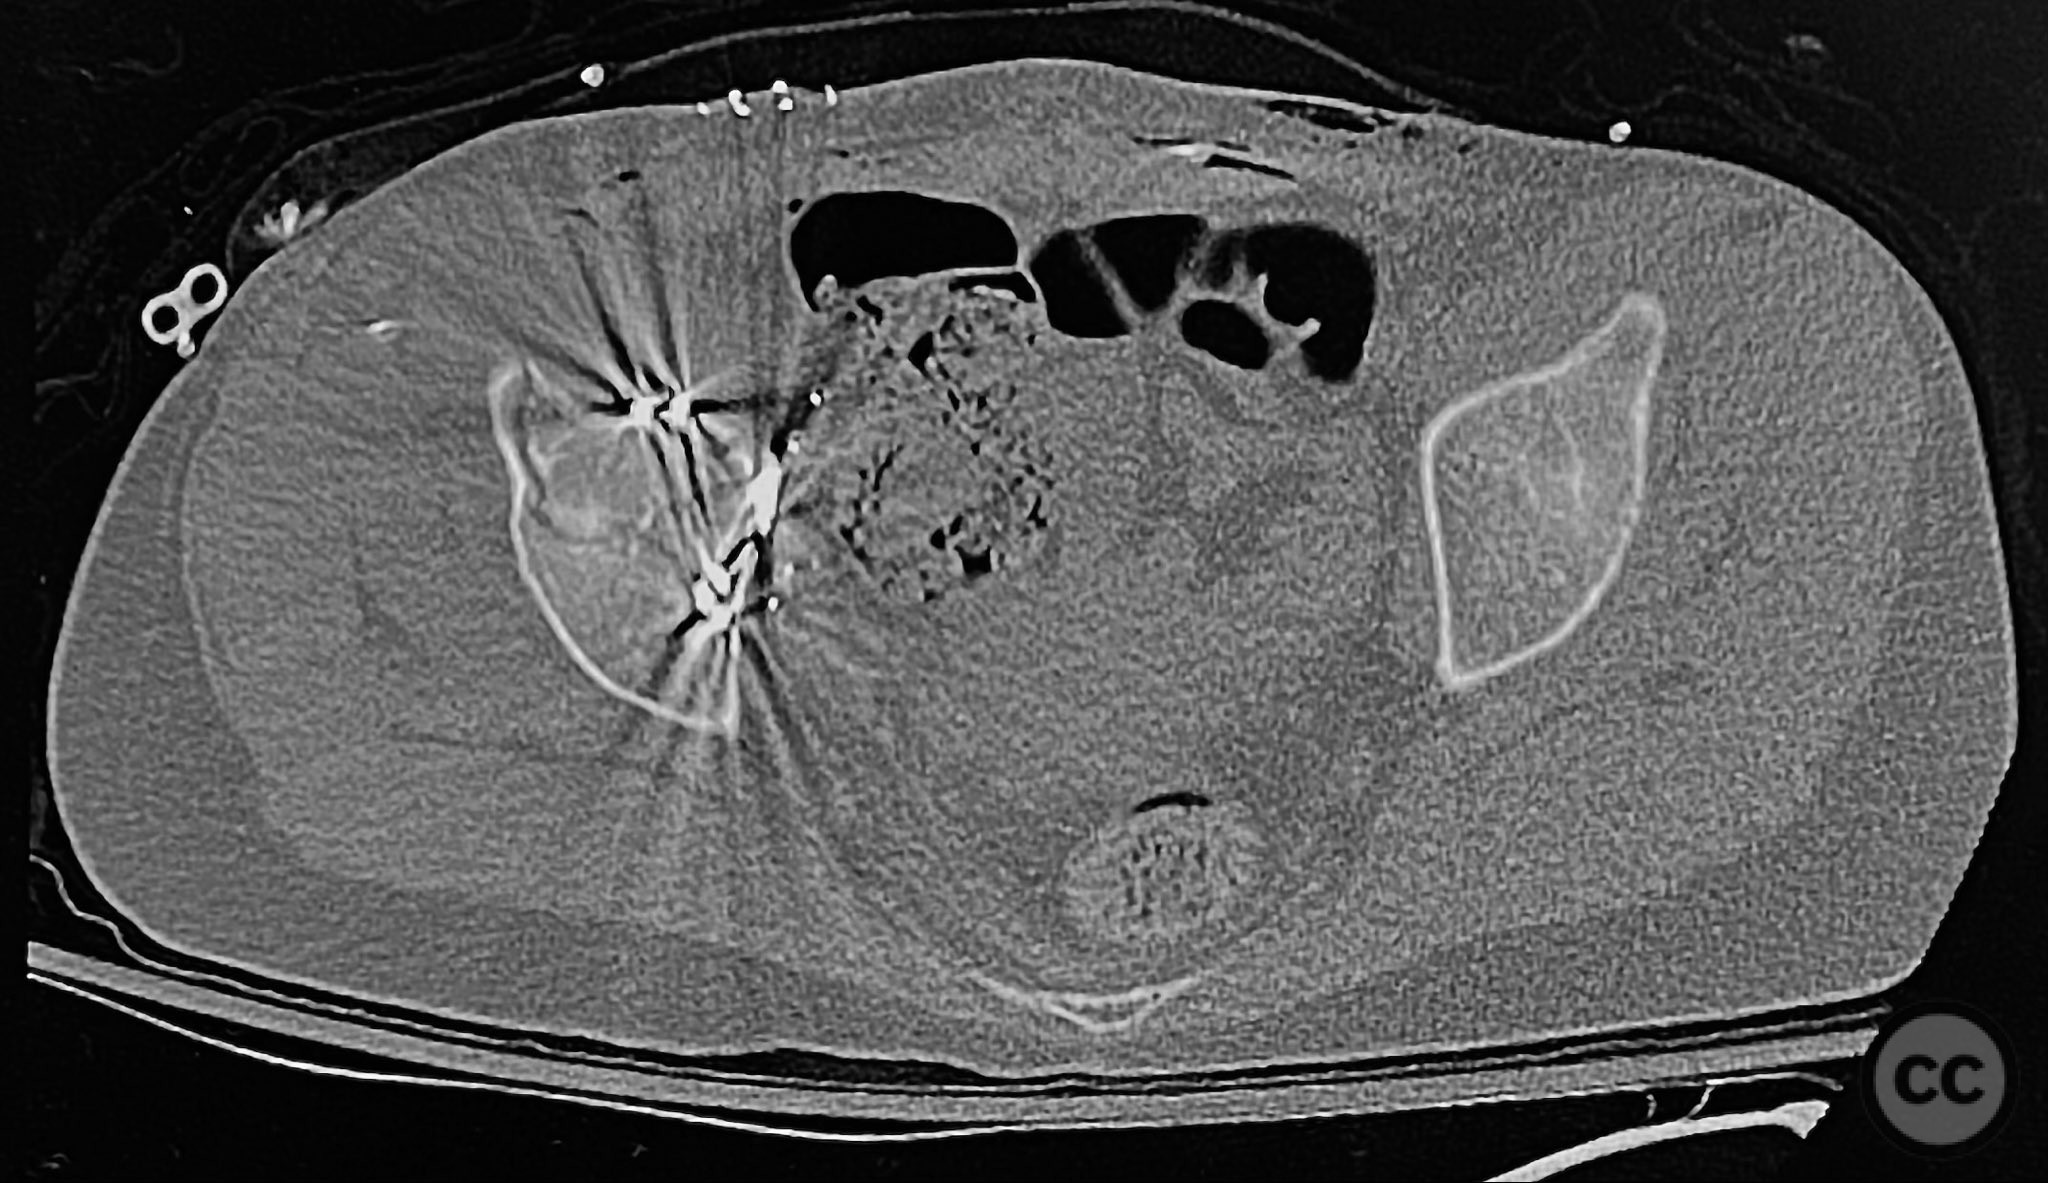

Clinical and radiological findings:  The patient sustained an acetabular fracture with a rare posterior medial dome impaction fragment, as demonstrated on AP pelvic radiographs obtained in skeletal traction. Surface renderings and axial CT images revealed multiple incomplete fracture lines, including a rhomboid-shaped cortical fragment adjacent and proximal to the anterior column/wall fragment. Coronal and sagittal reconstructions further delineated the impacted articular fragment and its relationship to the surrounding acetabular dome. The fracture pattern is classified as AO/OTA 62B3 (associated both-column fracture with dome impaction).

Anatomical surgical approach:  A classical ilioinguinal approach was performed, developing the lateral, middle, and medial windows. The intrapelvic interval was used to access the quadrilateral surface and posterior column. The rhomboid cortical fragment was excised to allow direct visualization and manipulation of the impacted posterior medial dome fragment. Reduction was achieved using a spiked pusher under fluoroscopic guidance. The defect was filled with morselized allograft, and the rhomboid fragment was anatomically reduced. The anterior column was stabilized with a contoured plate. Posterior column reduction was further improved using a reduction clamp applied with one tine lateral to the anterior inferior iliac spine (AIIS) and the other on the quadrilateral surface via the middle window, followed by lag screw fixation.